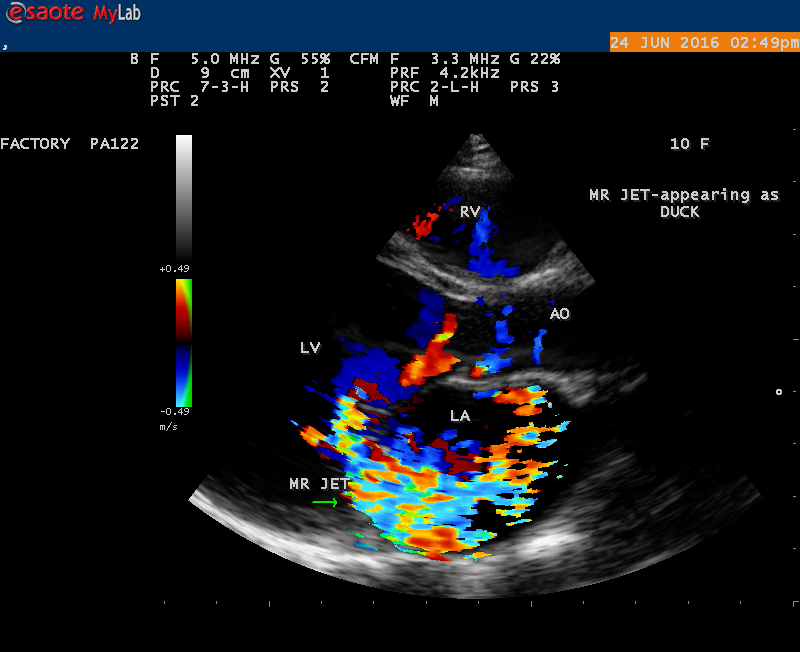

Echocardiography is the only noninvasive method available for direct visualization of endocarditis-induced lesions. Echocardiographic finding in patients with infective endocarditis was initially observed by Dillon [25] and Spangler, et al [26]. The vegetation will grow in size, either as a sessile clump or a highly mobile and even pedunculated mass with the potential for embolization. Vegetation can be detected when the valve attached mass reach a diameter of ≥ 2 to 3 mm [27]. In both children and adults, 2-D echocardiography is usually the more sensitive technique with sensitivity in children up to 80% [28]. Valvular dysfunction due to tissue disruption or large obstructing vegetation can be visualized and quantitated by echocardiogram with Doppler [29]. The detection of a large eccentric jet adhering, swirling, and reaching the posterior wall of the LA is in favour of significant MR (mitral regurgitation) as shown in Figures 22, 24 and 25.

The most common and direct evidence of infective endocarditis is the vegetation and it begins as a microscopic focus of infection and gradually grows into a conspicuous mass. It is typically an irregularly shaped, highly mobile, echogenic mass attached to the free edge of a valve leaflet ( most commonly at the coaptation line) and tends to develop on the ‘upstream’ side of the valve leaflets ( ie, the ventricular side of aortic valve and the atrial side of mitral and tricuspid valves. They may be seesile or pedunculated, but usually has an oscillating or fluttering motion, a typical feature of most vegetations. Vegetation move with the leaflet in a more chaotic (‘oscillating’) manner and it may prolapse through the valve into the LV (left ventricle) as it opens as shown in Figures 3, 4 and 16 and into LA (left atrium) as it closing (Figure 5 and 6) . The mass of vegetation is typically homogeneous with echogenicity similar to that of the myocardium. The infectious process often alter the valvular structure and function. Extensive involvement of the leaflet may result in chordal rupture, leading to severe regurgitation as shown in Figure 21 . Direct and typical signs of RMCT (ruptured mitral chordate tendineae) were chain-flail or whiplash-like changes and had an incidence of 86.7%, causing severe regurgitation and mitral chordal rupture is the leading cause of flail mitral leaflet[30]. A large vegetation may obstruct the valve orifice as shown in Figure 1 and 2 , sometimes termed as “obstructive-type bacterial endocarditis” and producing a functional valve stenosis ( Ping-Pong mitral stenosis [31]) similar to left atrial myxoma as shown in Figure 29.

The shape and size of vegetation are quite variable and mostly it is polypoid [32]. The typical vegetation is a ‘sessile’ or ‘ pedunculating’ valve – attached mass. A ‘sessile’ vegetation had to be completely attached to the valve as shown in Figures 34 and 35 in a 63- year old male, in which a large vegetation is attached to the atrial side of anterior mitral leaflet [33-Figure 13.3-A], producing severe mitral regurgitation as shown in Figure 36 and a mobile vegetation showed a pedunculating part prolapsing into the ventricle as shown in Figure 3 and 4 or atrium as shown in Figure 5 [33-Figure 13.1] in a 10-year old female child. A vegetation was considered as ‘definite’ when shaggy echoes in the M-mode study as shown in Figure 20 . and a corresponding mass without restricted valve motion in the two-dimensional echocardiogram were found as shown in Figure 16 and 30 [33-Figure 13.7]. The vegetation vary in size, often being just a few mm and sometimes reaching to 2-3 cm. A vegetation must be atleast 3 to 6 mm in size to be reliably seen. The mean size of vegetation was 0.6 mm (range 3 to 28) and vegetation > 10 mm in diameter was defined as ‘large’ and those ≤ 10 mm in diameter was defined as ‘small’ and ≥ 15 mm is ‘very large’. Vegetations resulting from fungal infections (candida, aspergillus) are usually much bigger than bacterial vegetations and can be so big to be mistaken for a cardiac tumor. The large vegetations are at increased risk for embolic complications [34], especially on the anterior leaflet of the mitral valve with mobility [35]. A vegetation size of 3.2 x 4.4 cm is called as ‘giant vegetation’ on the mitral valve with a fibrillary appearance of the mass [36- Figure 3] as shown in Figure 1 is an important predictor of embolic phenomena in patients with infective endocarditis causing severe mitral regurgitation as ‘Duck’ shaped jets (Figures 24 and 25 ), disorganized (Figure 21) and sometimes the regurigitant jet splits into two components as one into LA and the second one into LV simultaneously as a bileaflet jets (Figure 10 ) similar to bileaflet structure of AML with vegetation masses (Figure 9 ) . The size of the largest vegetation reported on the mitral valve in the literature in patients with bacterial endocarditis is 7x4 cm[37]. In a study of Nunes, et al[38], vegetation size >13 mm was the only independent predictor of mortality, but some studies [39],[40] did not had an increased embolic risk in patients with vegetation focused only on its presence and size and not on their location. Embolic complications may occur in infective endocarditis(20.6%)and were not more prevalent in the groups with large vegetations [41]. However, Wong, et al [42] found an increased need for surgery in patients with a large vegetation (>10 mm).

The shape of vegetation varies in this child as ‘popcorn’ like (Figures 1,3 and 4 ), rod-shaped (Figure ), basket shaped (Figure 7 )[33-Figure 13.3], ‘baby in hand’ appearance (Figure 18), ‘cucumber shaped (Figure 2 ) and a ‘bunch of plantain’appearance (Figure 33 ), ring shaped (Figure 19 }, bileaflet structure (Figure 9 )with bileaflet MR jet as shown in Figure 10 . and kissing forms (Figure 13 - parasternal long axis view, Figure 14 - apical four chamber view and Figure 15 - short axis view)

The anatomic disruption of a portion of the mitral valve apparatus dueto the underlying rheumatic valvulitis with predisposing infective endocarditis which form a vegetation , resulting an eccentric regurgitation jet with orientation opposite in direction of the leaflet having the anatomic defect such as ‘flail’. In the presence of ‘flail leaflet’, the mitral regurgitant spectral signal may have an atypical appearance and the flail portion oscillate in the spectral signal of regurgitant flow stream to produce a ‘tiger stripe’ appearance as shown in Figure 27. associated with ‘whistling’ sound on auscultation[33-Figure 11.85]. The mitral regurgitation (flail MR) jet is chaotic as shown in Figure 26, highly eccentric (Figure 22) and disorganized with one component behind the anterior mitral leaflet and the second component directed towards posterior immediately as in Figure 21 [33- Figure 11.79].

The severity of eccentric MR is underestimated because of coanda effect. If the regurgitant jet area fills < 20> 40% indicate severe regurgitation. The vena contracta ( the neck or narrowest portion of the jet), typically imaged perpendicular to the commissural line in parasternal long axis and apical four chamber views is well defined in both central and eccentric jets, but not in chaotic, disorganized jets due to flail leaflets. Its width < 3> 7 mm defines severe MR and a mean value of > 8mm indicates severe functional MR. The flow convergence method based on PISA (proximal isovelocity surface area) may not applicant for eccentric and multiple jets or complex and elliptical regurgitant orifices to assess the severity of mitral regurgitation.. The adaptation of LV to the increased volume overload is reflected by LV dimensions and ejection fraction.. In chronic compensated phase, the forward stoke volume is maintained through an increase in LV ejection fraction >65% and the patient could be asymptomatic. In chronic decompensated phase of MR, the forward stroke volume decreases and the LA pressure increase significantly. The patient may be still asymptomatic and the LV ejection fraction may be in the low normal range despite the presence of significant muscle dysfunction. The contractile function decreases silently and become irreversible. In the current guidelines, surgery is recommended in asymptomatic patients with severe organic MR when the LV ejection fraction is ≤ 60%. However, in acute stage, the LV ejection fraction increases in response to the increased preload. The end-systolic diameter is less preload dependent than the ejection fraction and it may be more appropriate to monitor the global LV function. The end-systolic diameter > 45 mm also indicate the need for mitral valve surgery [43]. In this child, the LVESD (end-systolic diameter) is 30.7 mm and the ejection fraction (EF) is 66% as shown in Figure 19. New parameters are currently available for a better assessment of LV function. A systolic tissue Doppler velocity measured at the lateral annulus <10>40-50mm) may predict the onset of atrial fibrillation and poor prognosis in patients with organic MR[48]. The excess regurgitant blood entering in the LA may induce acutely or chronically a progressive rise in pulmonary pressure and the presence of TR (tricuspid regurgitation) as shown in Figures 26 and 28 permits the estimate of systolic pulmonary arterial pressure and mitral valve surgery is recommended when it is > 50 mmHg at rest and LA reverse remodeling may occur after surgery. The severe TR may cause a decrease in hepatic vein systolic velocity and systolic flow reversal may occur as shown in Figure 32 and its sensitivity is 80% [49]. The TR (tricuspid regurgitation) jet velocity in this child is 4.03 m/s as shown in Figure 28 which corresponds to a systolic pulmonary artery pressure of 65 mmHg.